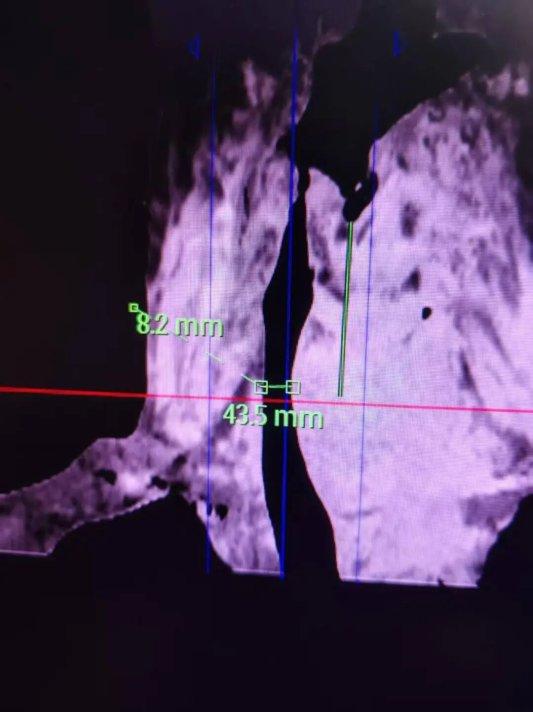

该患者病情极为复杂,巨大甲状腺肿长期压迫气管,致气道严重移位、狭窄,最窄处仅8mm,气管软骨受压变形,随时有窒息猝死风险。同时,患者合并高血压、老年性肺功能减退,心脏功能减退、脏器储备功能极差,麻醉与手术风险极高。

术前,淄博一四八医院麻醉科多次组织专题研讨,仔细研读影像学资料,全面评估气道与身体状况,梳理各类高危风险,制定“快速顺序诱导插管+多模态循环监测+紧急气管切开备用”的三重保障方案,筑牢术前风险防控屏障。